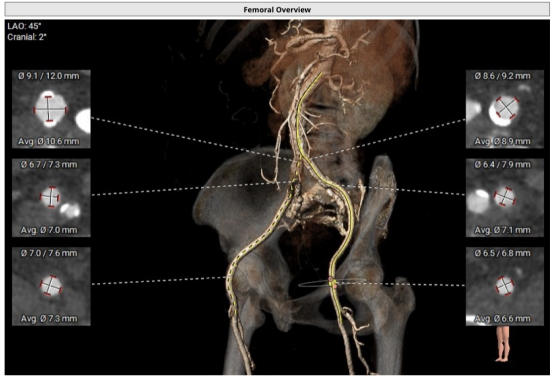

全主动脉入路CT评估

图片

采用镇静加局麻的方式,经由右侧股动脉置入20F大鞘,20mm球囊扩张前测跨瓣压差80mmHg,选用MuguetA™ 23mm瓣膜,标准体积+1cc充盈,180bpm快速起搏下精准释放,手术位置理想(90/10%),主动脉根部造影提示微量瓣周漏,压差完全消失,冠脉开口通畅,心电图提示传导系统无影响,复查造影右股动脉未见明显狭窄,无造影剂外渗无夹层,手术效果良好。